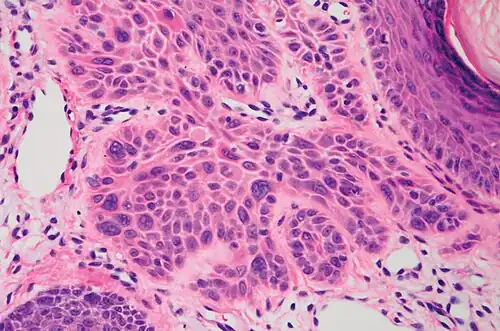

In invasive cSCC, tumor cells infiltrate through the basement membrane. The infiltrate can be somewhat difficult to detect in the early stages of invasion: however, additional indicators such as full-thickness epidermal atypia and the involvement of hair follicles can be used to facilitate the diagnosis. Later stages of invasion are characterized by the formation of nests of atypical tumor cells in the dermis, often with a corresponding inflammatory infiltrate.[12]

-

Superficially invasive cutaneous squamous-cell carcinoma. These lesions often do not show the marked pleomorphism and atypical nuclei of cSCC in situ, but manifest early keratinocyte invasion of the dermis.[12] -

High magnification demonstrates the pleomorphism of the invading keratinocytes[12] -

Invasive nests with characteristic large celled centers. Ulceration (at left) is common in invasive cSCC.